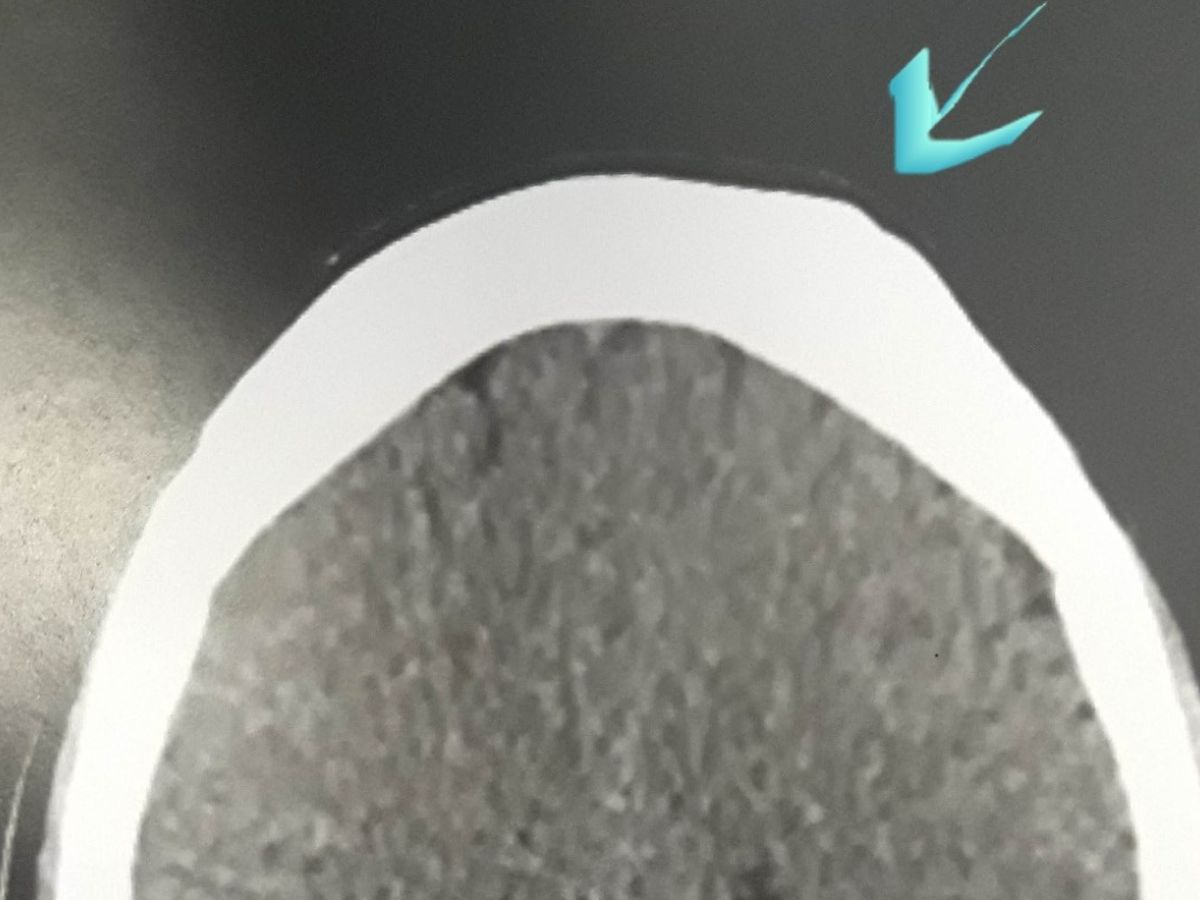

Cranial Surgery needed on upper forehead

CTSCAN